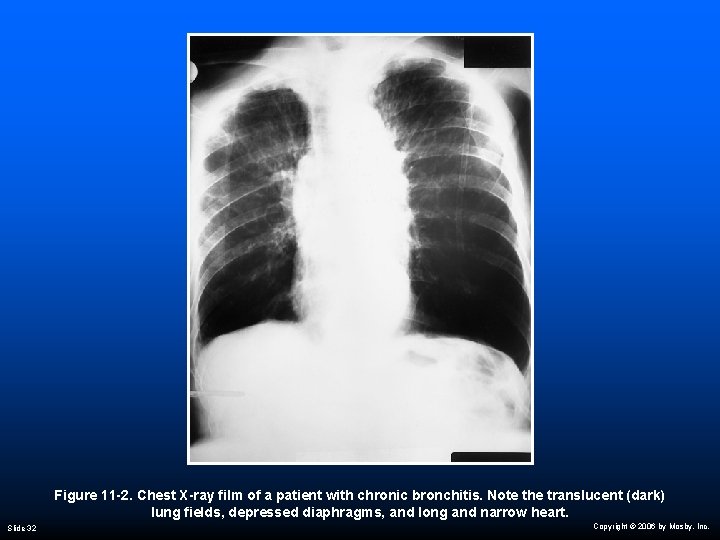

Radiologic Findings Chest radiograph Slide 31 Translucent (dark) lung fields Depressed or flattened diaphragms Long and narrow heart Enlarged heart Copyright © 2006 by Mosby, Inc.

Figure 11 -2. Chest X-ray film of a patient with chronic bronchitis. Note the translucent (dark) lung fields, depressed diaphragms, and long and narrow heart. Slide 32 Copyright © 2006 by Mosby, Inc.